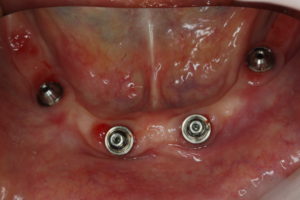

インプラントを長持ちさせるためにはメインテナンスは欠かせません。今回は、ちょうど1年経過したため念のため、ねじを外して上部構造と呼ばれる歯の部分の裏側の汚れを確認しました。

わずかに汚れは付いているものの、炎症を起こすような状態ではありませんでした。患者さんのお掃除の賜物です。